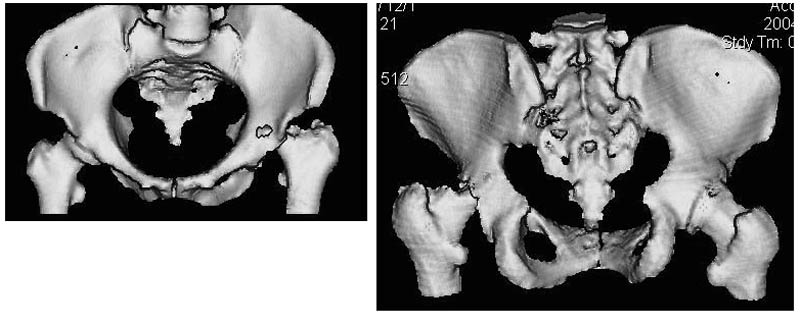

Женщина, 45 лет. В марте перенесла левосторонний коксит неизвестной этиологии. Специфику и онкологию исключили.

Интраартикулярных инъекций не было. Сейчас процесс клинически и рентгенологически - стабилизировался. Состояние вполне удовлетворительное.Предполагается тотальное эндопротезирование с пластикой полости аутокостью. Возможна ли бесцементная <чашка>? Заранее благодарю! С уважением,А.В.Владзимирский

Дополнение - проконсультировался с женой-она специалист рентгенолог - на КТ большое колиество мягкотканного компонента - ищите микоплазмы или бруцеллу. Я склоняюсь к виопсии.

Пртезирование через пол года после коксита закончившегося лизисом сустава, который на снимках выглядит как гнойный? Что значит неизвестной этиологии?

Уважаемый коллега! Последняя версия - мы пролистали ренгенологическую книженцию-так картинка вполне подходит под сустав Шарко (neuropatic joint ). В тазобедренном суставе патология редкая (но меткая). Ищите причину - варианты - нейросифилис, сирингомиелия, опухи спинного мозга (и выше тоже) компрессия спинного